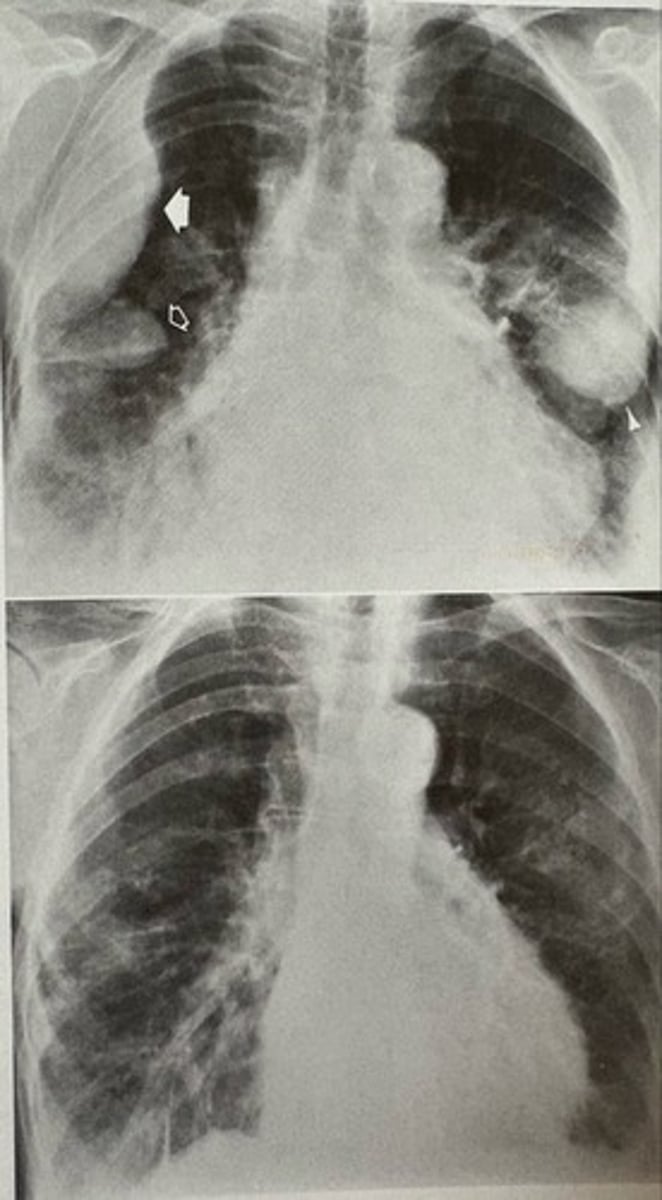

loculated pleural effusion (phantom tumor)

what pathology is present?